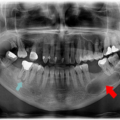

همین باکتری های پلاک و تارتار در دراز مدت باعث ایجاد حفره و پوسیدگی دندان می شوند. با توجه به اینکه پوسیدگی دندان یکی از شایع ترین بیماری های دهان و دندان کودکان است و احتمال ابتلای آنها به پوسیدگی زودتر بیشتر است، بخش اساسی هر معاینه منظم، یافتن پوسیدگی و حفره ها قبل از بدتر شدن آنهاست.

خوشبختانه، شناسایی مشکلاتی مانند حفره ها در مراحل اولیه که می توان سریعتر متوقف یا مدیریت کرد، آسان تر است. در حالی که نادیده گرفتن حفره ها به آن ها اجازه می دهد تا رشد کنند و به ساختار دندان آسیب بیشتری وارد کنند، که منجر به عفونت ها و روش های پیشرفته دندانپزشکی مانند پر کردن و کشیدن دندان در دوران نوجوانی می شود.